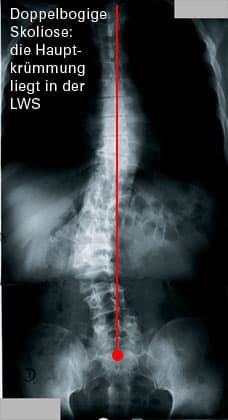

S-förmige oder C-förmige seitliche Verbiegung der WS (bei der Betrachtung von hinten) in Verbindung mit einer Verdrehung der WS in sich selbst (Torsion).

Die Torsion ist verantwortlich für die Asymmetrie des Rückens, die vor allem bei der Rumpfbeugung auffällt: einseitiger Rippenbuckel, Lendenwulst, oder die Kombination von beiden.

Jede Skoliose hat einen Hauptbogen, der wegen der Statik funktionelle Gegenbögen auslöst. Die Schwere der Skoliose wird nach der Krümmung des Hauptbogens eingeteilt. Danach richtet sich die Therapie.